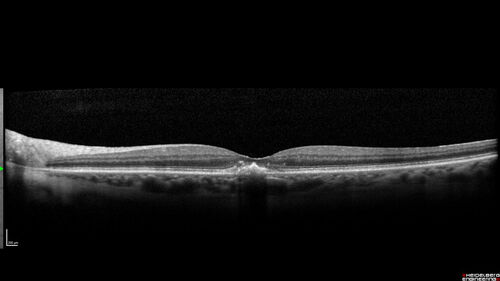

Pattern Dystrophy with Collapsed Vitelliform

74 year old female with vision loss in eye with collapsed vitelliform lesion.